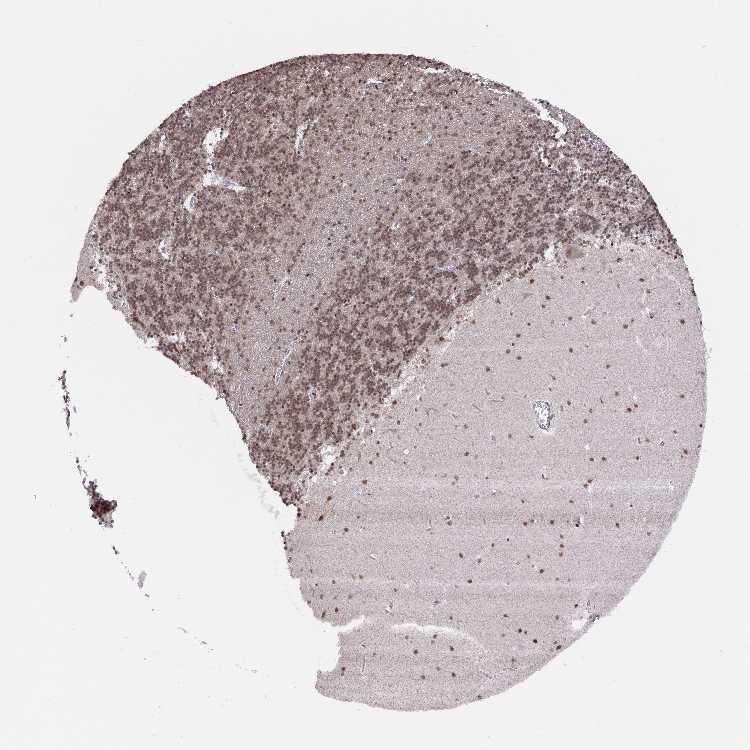

BRAIN CEREBELLUM Show tissue menu

CEREBELLUM - Expression summary

Protein expression

Cerebellumi

On the top, protein expression in current human tissue, based on all annotated cell types, is reported with the units not detected (n), low (l), medium (m) and high (h). Underneath, protein expression in each annotated cell type are reported using the same units.

Protein expression data is based on knowledge-based annotation. For genes where more than one antibody has been used, a collective score is set.

If knowledge-based annotation could not be performed for a gene, no data is displayed here. View antibody staining data further down this page.

Cells in granular layer: Medium

Cells in molecular layer: Medium

Purkinje cells: High

CEREBELLUM - Antibody stainingi

Antibody staining in the annotated cell types in the current human tissue is reported as not detected, low, medium, or high, based on conventional immunohistochemistry profiling in selected tissues. This score is based on the combination of the staining intensity and fraction of stained cells.

Each image is clickable and will lead to virtual microscopy that enables deeper exploration of all samples and also displays staining intensity scores, fraction scores and subcellular localization as well as patient and tissue information for each sample.

Antibody HPA042843Antibody HPA049439

Purkinje cells HighHigh

Cells in granular layer MediumHigh

Cells in molecular layer MediumMedium